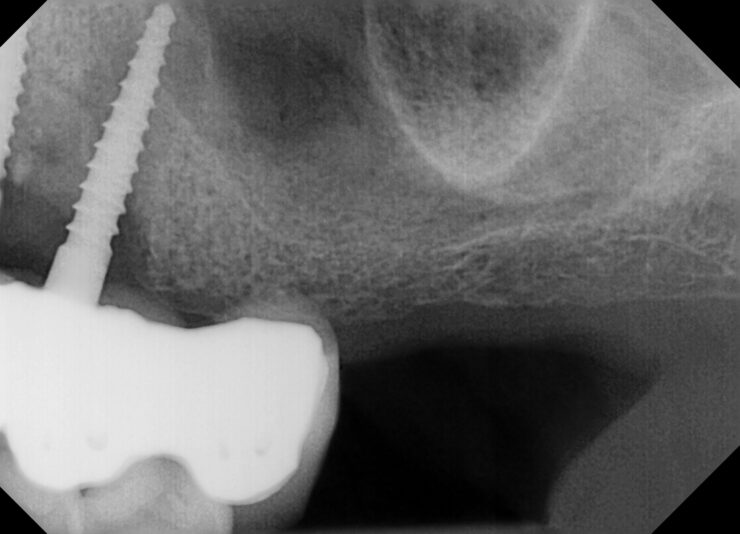

• I know this is an implant study club but I wanted to share a disappointment I had in my most recent bone graft. Patient came in for second opinion and after going over options and non restorable #31 I extracted and grafted the site. Post op PA showed that the M canal and defect was still present. This did have a buccal wall defect and I placed…

Read more